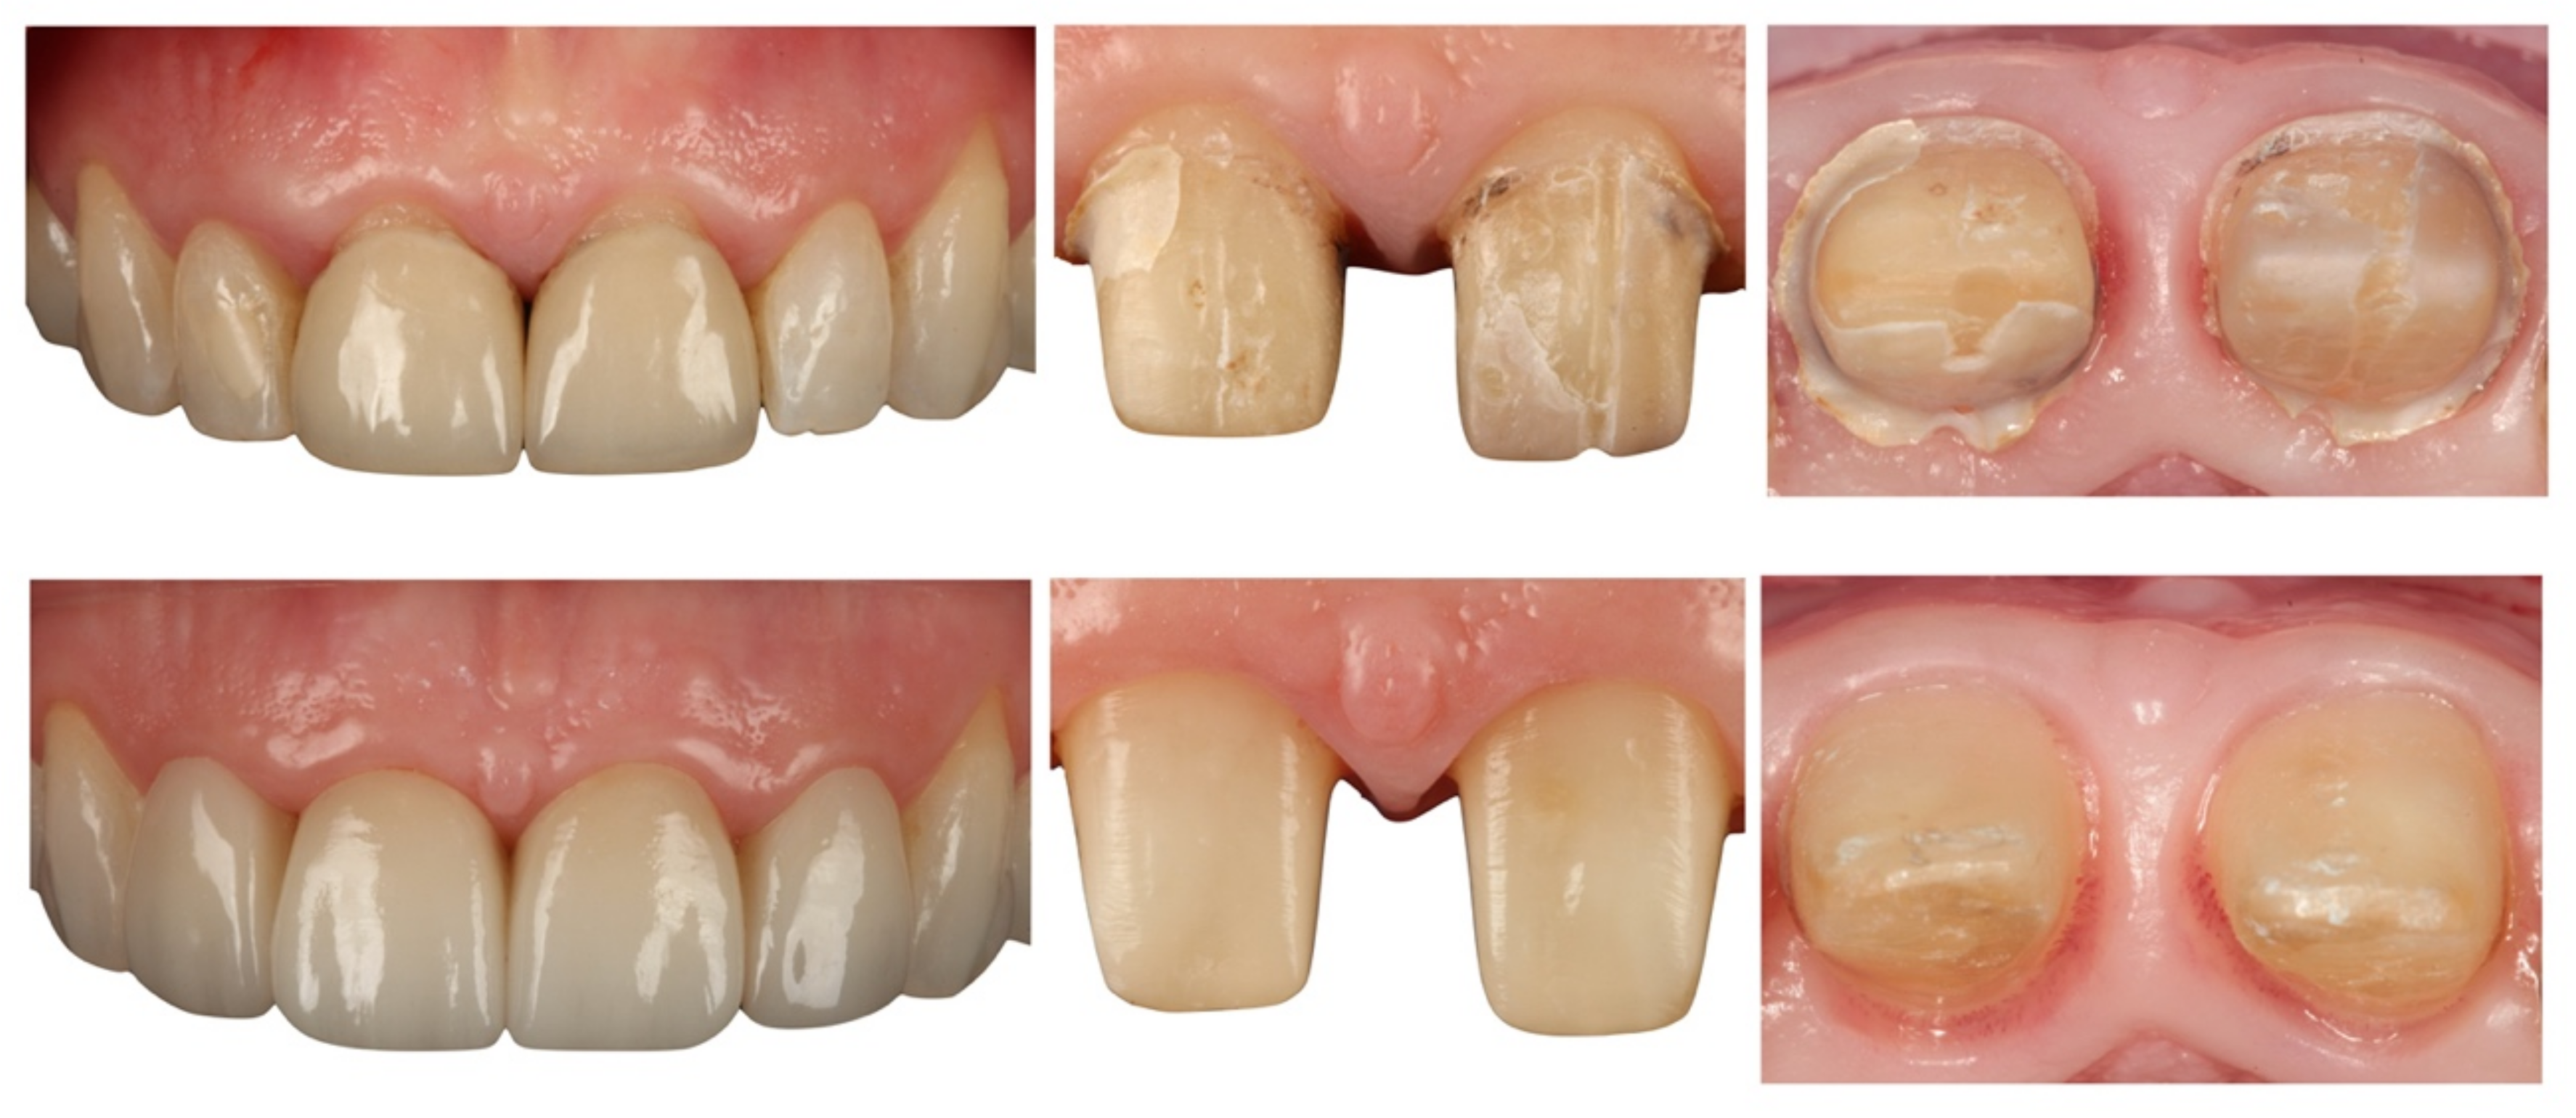

- Treatment with single zirconia crowns on teeth prepared with BOPT obtained an accumulated survival rate of 97.2%. Accordingly, the incidence of biological or mechanical complications was not statistically significant and the restorations presented good behavior over the 6-year follow-up.

- Teeth treated with this technique presented improved plaque indices, stable probing depths, increased gingival thickness, and stable gingival margins over the 6-year follow-up.

- Treatment with a fixed prosthesis using the BOPT technique has a positive impact on patient satisfaction, especially in cases concerning the re-treatment of old fixed prostheses. This fact is due to the esthetic improvement not only of the restoration but also of the surrounding tissues, as it improves gingival quality by thickening the tissue, thus preventing gingival recession.